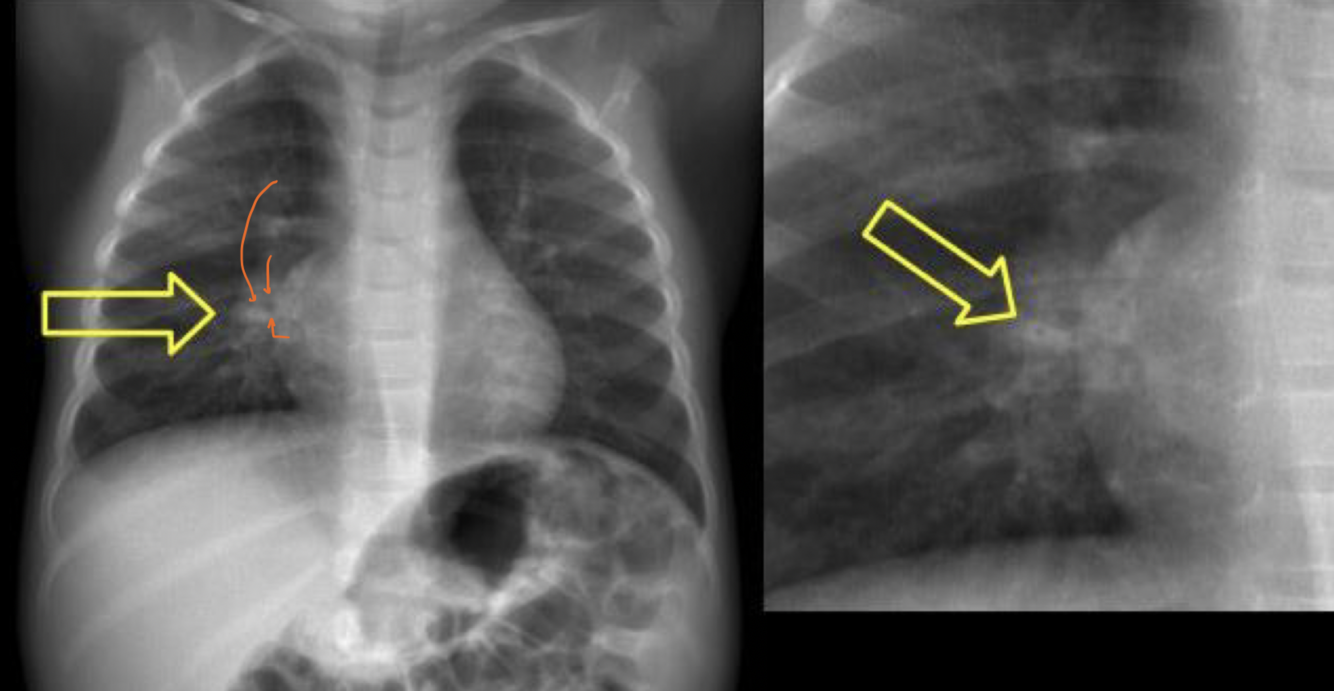

Q

Patrón que podemos ver

A

Centrolobulillar

Paraseptal

Panlobulillar